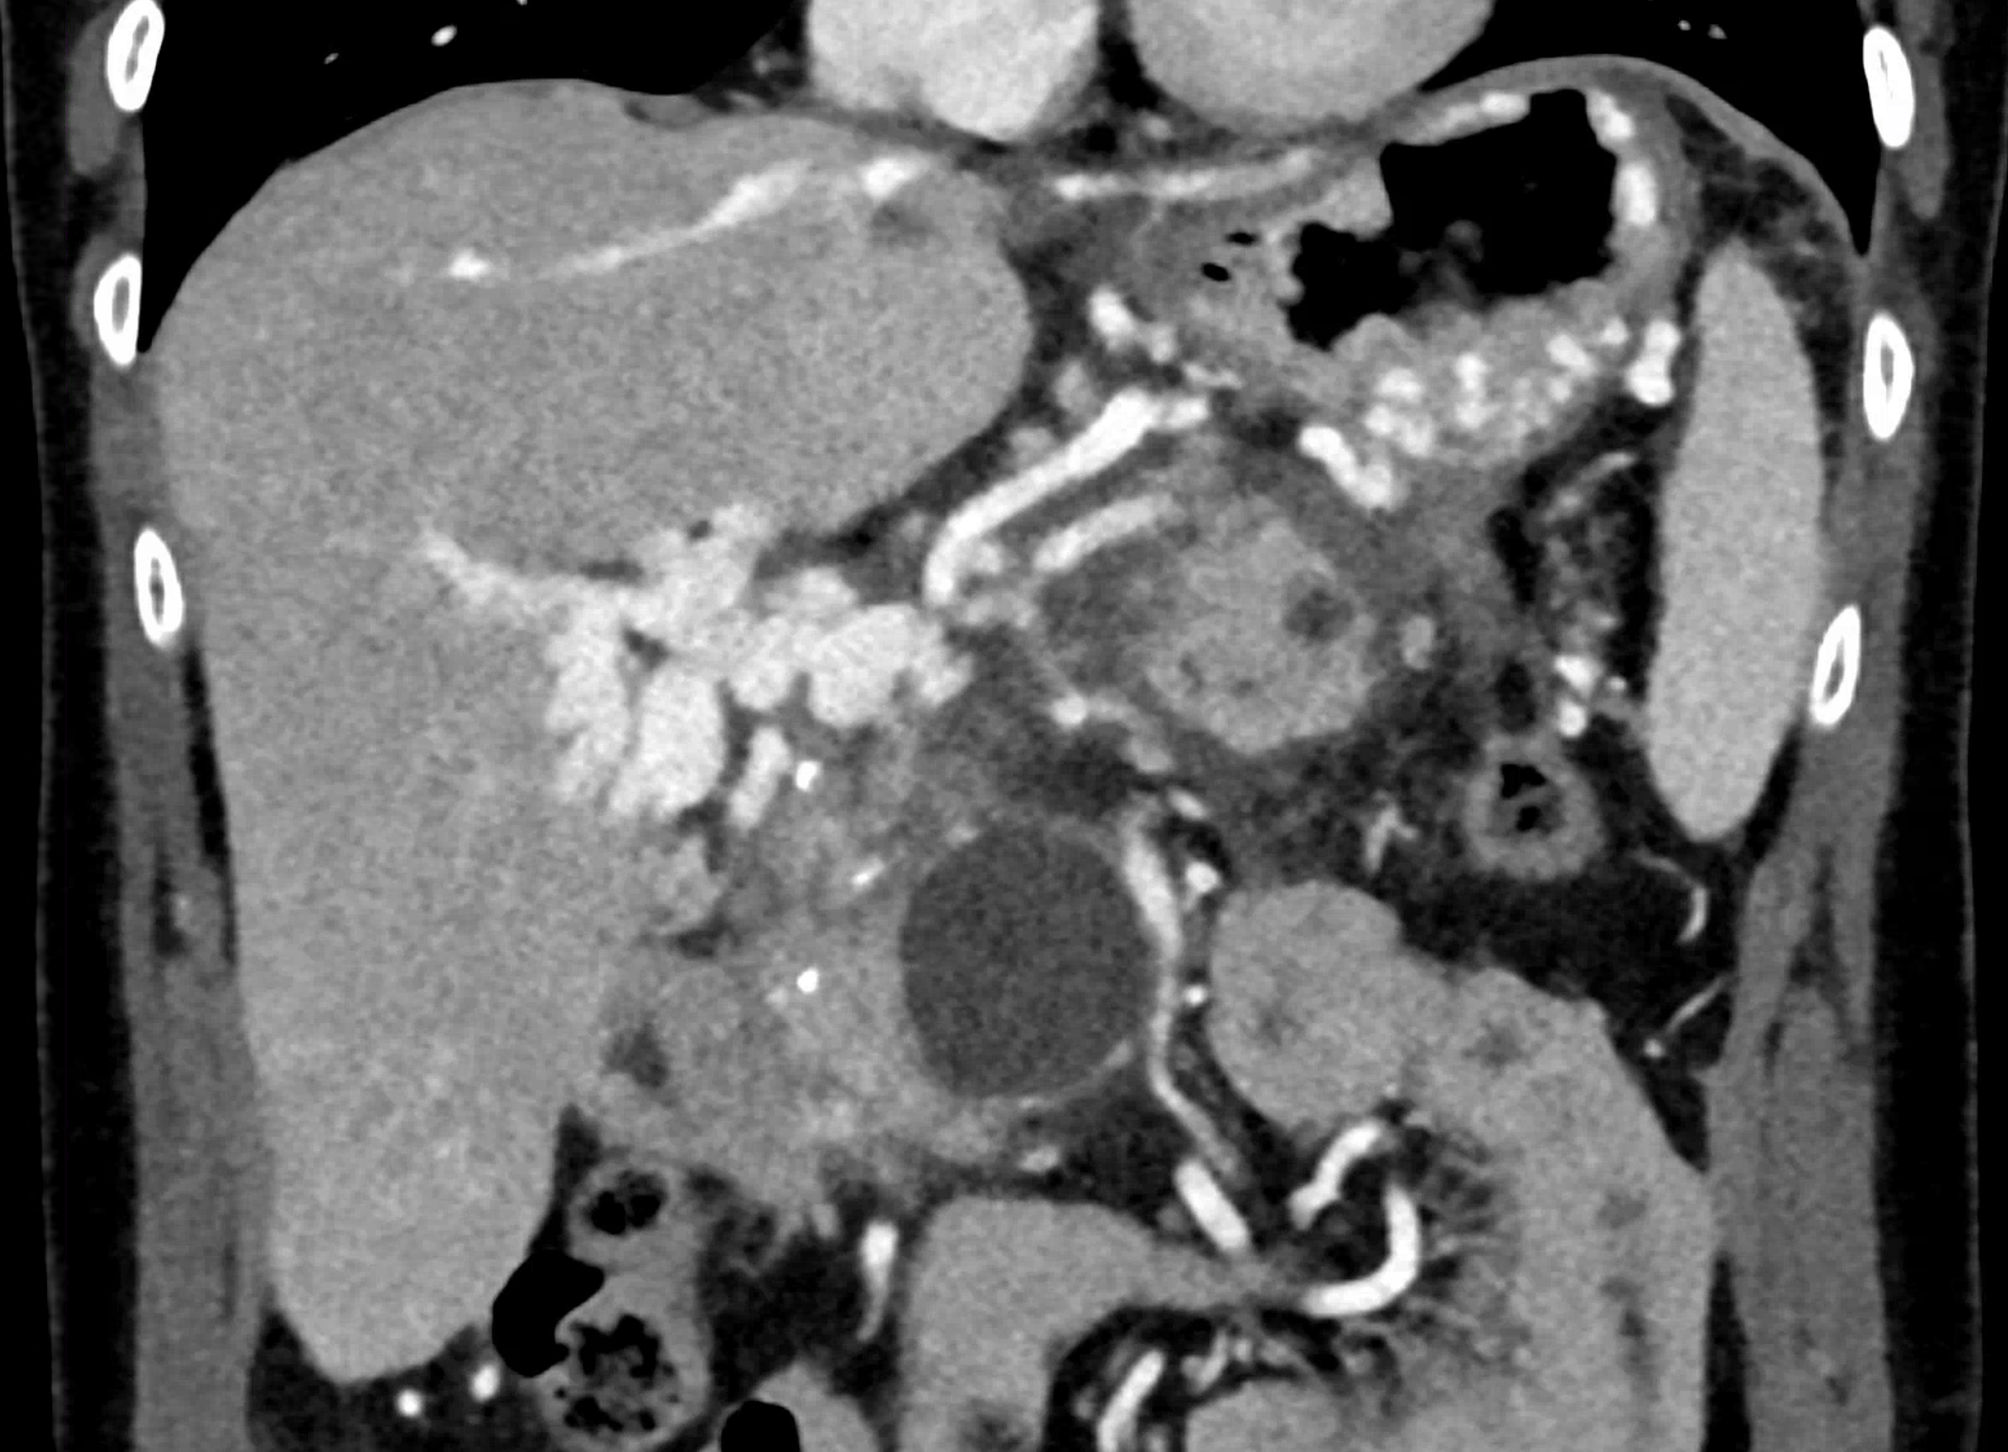

A patient with chronic pancreatitis and chronically occluded portal vein. The bile ducts have a significantly dilated wall, from the trunk, through the stump of the cystic duct, to the right and especially the left branch of the hepatic duct. At the same time, a large pseudocyst in the pancreas, dilatation of the pancreatic duct, and chromic occlusion of the superior mesenteric vein, splenic vein, and portal vein trunk are evident. Along with portal biliopathy, there is also arixy of the cardia and esophagus, as well as cavernous remodeling of the portal circulation itself.

volume rendered image after bone removal

volume rendered image after bone and kidney removal showing best the portal biliopathy